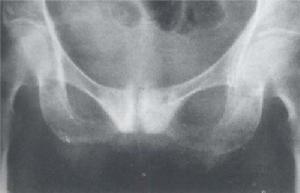

X線檢查有助於診斷受累及病灶區。骨端受累、溶骨區界限銳利、楔形透光區、廣泛性硬化、骨體積增大、骨小粱變粗等有助於與其他疾病鑑別。廣泛的骨密度增加應與骨轉移癌(尤其是前列腺癌骨轉移)、骨髓纖維化、腎性骨病、氟骨症、纖維異常增殖症和結節性硬化症鑑別。變形性骨炎累及顱骨時可出現顱骨肥大,應與額骨內板肥厚症、纖維異常增殖症、貧血和骨轉移癌等鑑別。本病盆骨硬化呈非對稱性或單側分布、受累骨增大、骨小粱增粗。累及脊椎時,病變椎體呈框架征,四周濃密。血管瘤所致者表現為縱向骨小粱增粗,腎性骨病除有腎臟本身的疾病外。特徵為橄欖球衣狀脊椎。

X線的表現較複雜可歸納為下列數點:①骨質破壞骨小梁粗糙稀疏伴局限性骨質疏鬆晚期的骨皮質與髓質腔界限不清,結構模糊如網狀;②骨幹增粗,膨大,彎曲變形,呈腰刀狀;③顱骨局限性骨質疏鬆伴棉絮狀增生,內外板界限消失,顱縫模糊,頭顱增大;④椎體呈柵欄狀和方框狀改變;⑤長骨溶骨性病灶有時呈V形;⑥骨盆連緣和弓狀線增厚,出現邊緣征;⑦髖關節間隙變窄,骨質增生短骨增粗;⑧病變區病理性骨折。